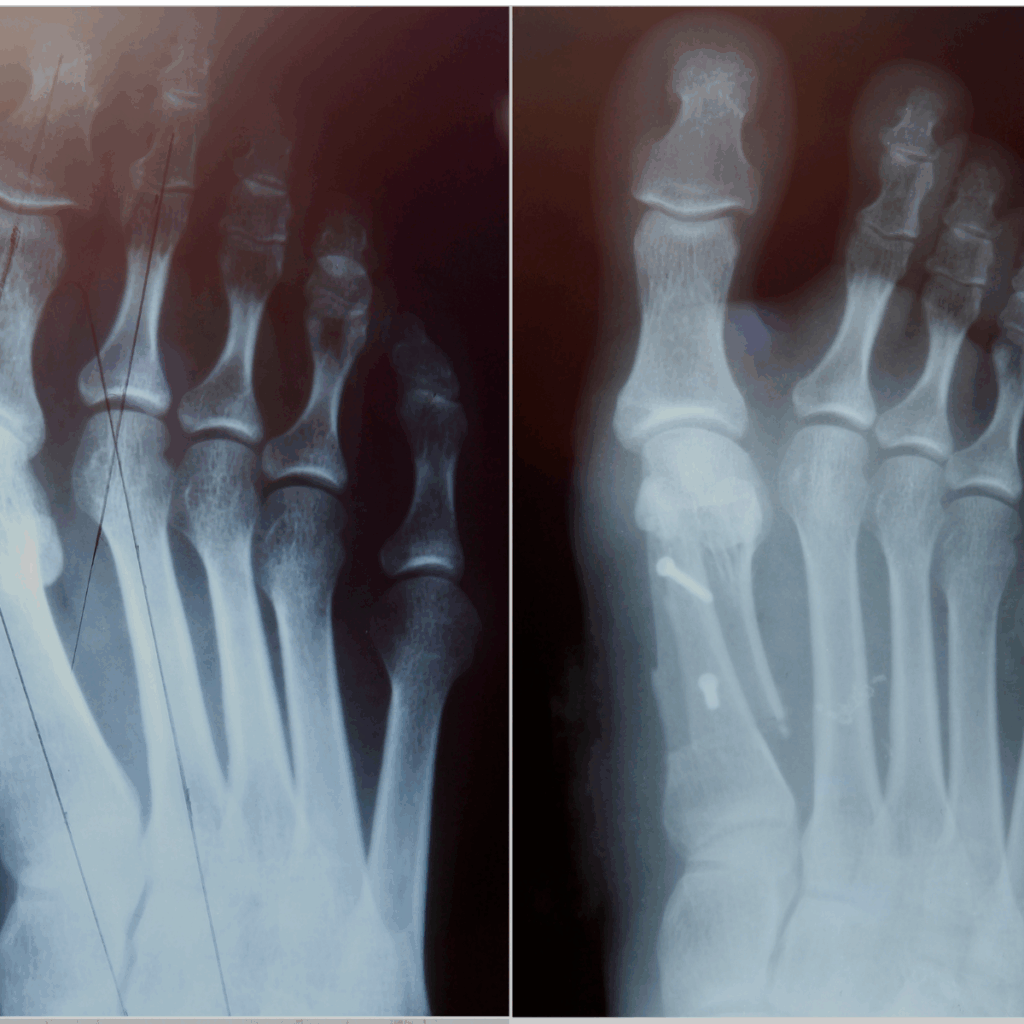

Foot & ankle deformities

a. Osteotomy (Bone Realignment Surgery)

The surgeon cuts and repositions the bone to correct alignment.

c. Internal Fixation (Plates, Screws, Nails)

Used for precise correction and stabilization of the bone.